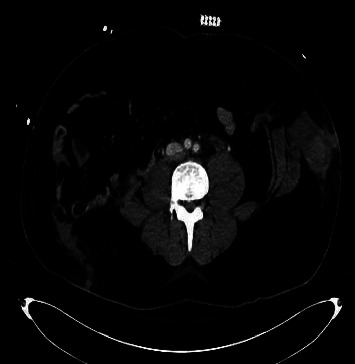

加勒特和布劳恩斯坦提出了机动车碰撞(MVC)受害者 "安全带征兆 "的概念。他们将其定义为腹带造成的腹壁瘀伤。这些创伤征兆并不少见。然而,"安全带综合症",一种因安全装置产生的减速力而导致的肌肉骨骼和内脏器官损伤的模式,却很少见。在此,我们展示了一例因安全带损伤而导致的腹直肌创伤性闭合性断裂。识别这种潜在的损伤非常重要,我们的病例将说明有必要进行仔细的影像检查和临床评估,以识别相关的腹内损伤。

Garrett and Braunstein introduced the concept of the "seat belt sign" in motor vehicle collision (MVC) victims. They defined this as abdominal wall bruising from a lap belt. These signs of trauma are not uncommon. However, "seat belt syndrome," a pattern of musculoskeletal and internal organ injuries resulting from deceleration forces exerted by the safety device is rarely seen. Here, we illustrate a case of traumatic closed rupture of the rectus abdominis muscle secondary to seat belt injury. This potential injury is important to recognize and our case will illustrate the need for careful imaging review and clinical assessment to identify associated intra-abdominal injuries.